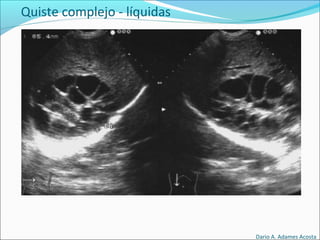

Quistes complejos

Quiste complejo - líquidas